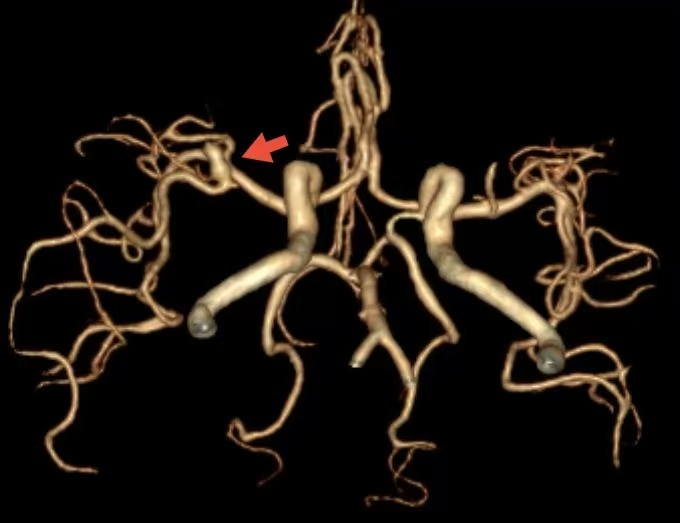

患者男性,40岁,既往体健。主因“头痛2天,加重1天”就诊于清华大学附属垂杨柳医院急诊科。查体:嗜睡,可对答,双侧瞳孔等大。急诊头颅CT显示蛛网膜下腔出血,CTA提示右侧大脑中动脉M1段分叉动脉瘤。

CTA提示右侧大脑中动脉动脉瘤